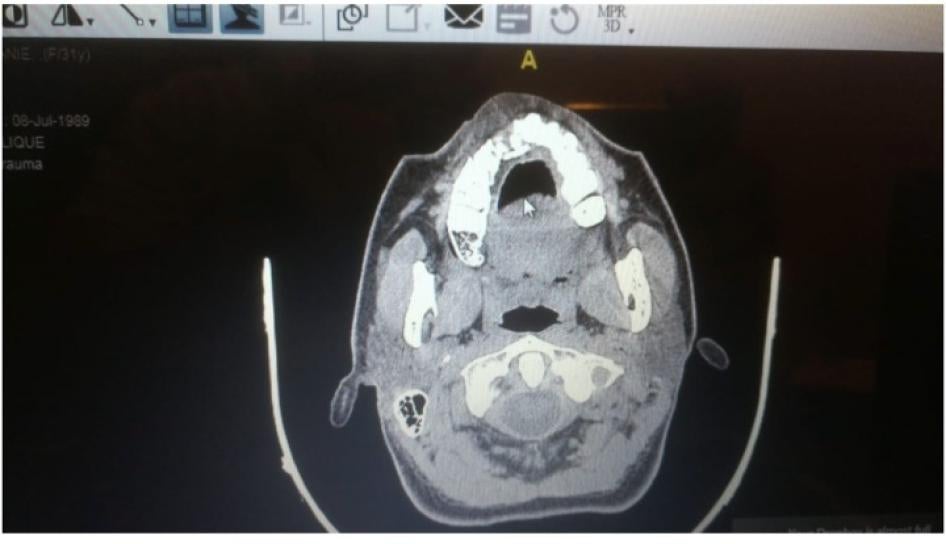

For the first time in Lebanon, Human Rights Watch documented several instances of Lebanese security forces using shotgun-fired metal pellets that wounded people. In some cases, security forces fired toward people’s upper bodies, including the head and face. Human Rights Watch reviewed medical records and X-rays, spoke to 3 victims and 4 doctors who treated them, and analyzed a pellet recovered from one person’s body, as well as a photograph of another. Additionally, the “White Shirts” doctors shared anonymized medical records of 13 patients seriously injured by the metal pellets.

Another doctor shared the anonymized X-rays of a patient who was wounded by dozens of pellets. The doctor said that the number of pellets and the fact that they punctured the patient’s scalp indicate that security forces shot at the person’s face from a very short distance. The pellets embedded under the sinus in the skull and in the protester’s eye, the doctor said.